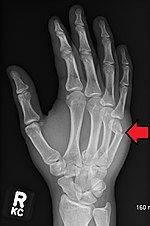

Boxer's fracture Boxers fracture at the neck of the fifth metacarpal punching solid object Boxer's fracture Archived 2007-07-15 at the Wayback Machine at Wheeless' Textbook of Orthopaedics online Fractured5thMetacarpalHead2018.jpg